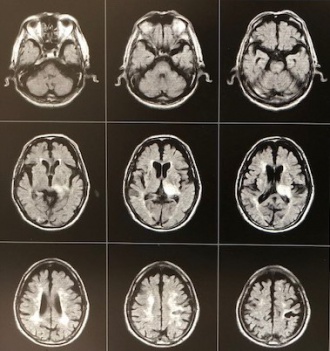

診察所見では、手足の麻痺は無く歩行もできていますが、ぼーっとした感じでした。緊急で頭部MRI検査を施行し、脳出血を認めました。すぐに総合病院に紹介しました。認知症の原因はいろいろありますが、このように急に症状が進行する場合は脳卒中が原因のこともあります。早めに受診をお勧めします。MRI画像で赤くマルの部位が脳出血したところです。